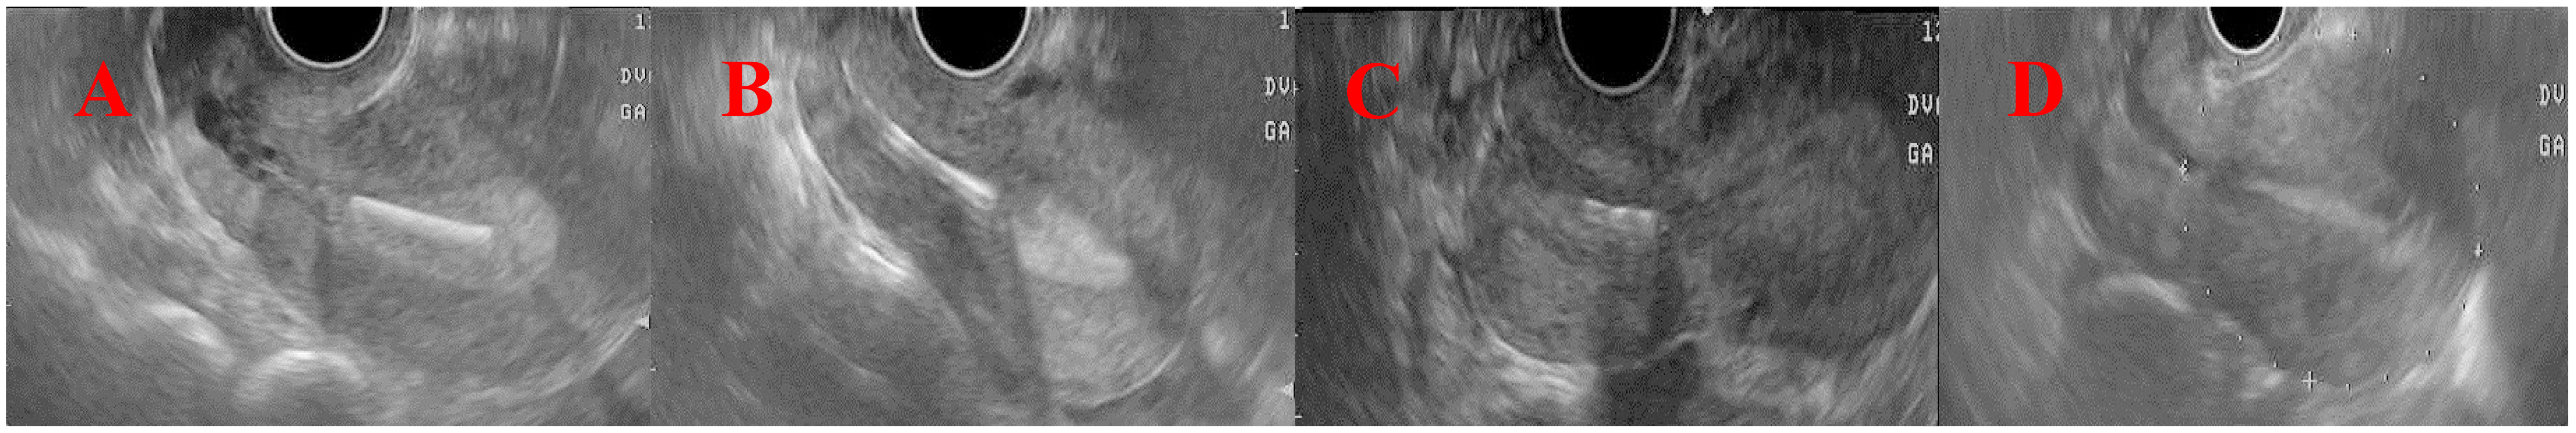

Fig. 3.Illustration of abnormal copper intrauterine device

positions. (A) Group 1: patients whose IUD fundus distance was